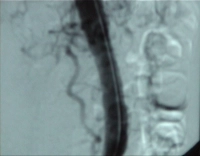

Filmbeispiel: abgangsnaher Verschluss der AMS mit Verschluss des Truncus coeliacus